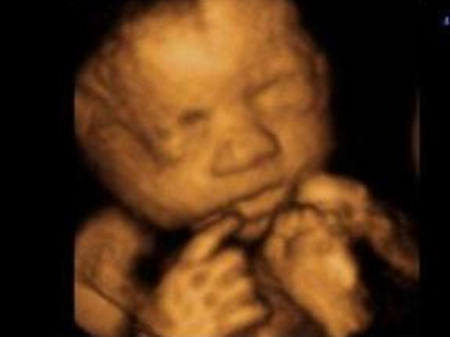

最后来个可爱的四维照!

有没有觉可爱到爆!